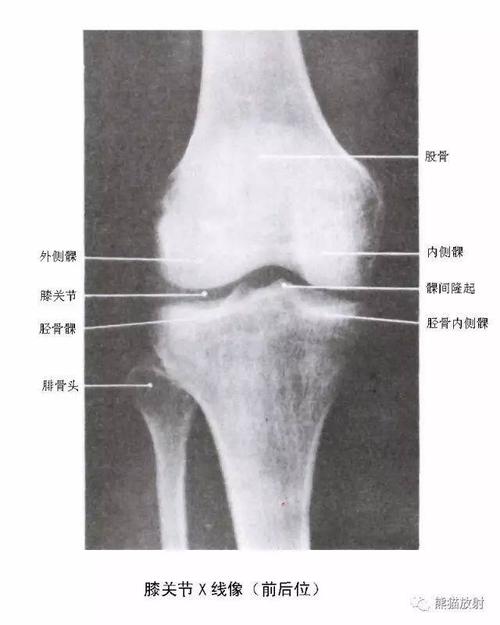

胫骨内侧髁

胫骨内侧髁,胫骨内髁

髌骨与股骨的髌面相接,股骨的内,外侧髁分别与胫骨的内,外侧髁相对.

胫骨近侧端膨大,向两侧突出成为内侧踝与外侧髁. /p>

胫骨内侧髁位置

胫骨内侧髁位置图

胫骨内侧髁位置图片